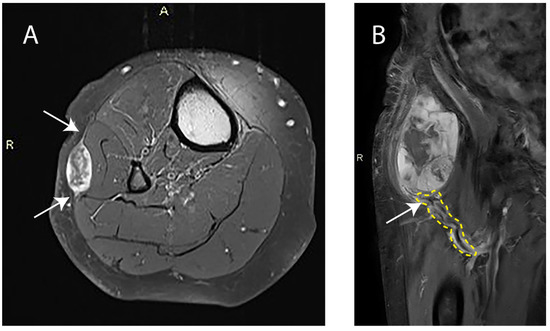

- Yoo, H.J.; Hong, S.H.; Kang, Y.; Choi, J.Y.; Moon, K.C.; Kim, H.S.; Han, I.; Yi, M.; Kang, H.S. MR imaging of myxofibrosarcoma and undifferentiated sarcoma with emphasis on tail sign; diagnostic and prognostic value. Eur. Radiol. 2014, 24, 1749–1757. [Google Scholar] [CrossRef]

- Kikuta, K.; Kubota, D.; Yoshida, A.; Morioka, H.; Toyama, Y.; Chuuman, H.; Kawai, A. An analysis of factors related to the tail-like pattern of myxofibrosarcoma seen on MRI. Skeletal Radiol. 2015, 44, 55–62. [Google Scholar] [CrossRef]

- Lefkowitz, R.A.; Landa, J.; Hwang, S.; Zabor, E.C.; Moskowitz, C.S.; Agaram, N.P.; Panicek, D.M. Myxofibrosarcoma: Prevalence and diagnostic value of the "tail sign" on magnetic resonance imaging. Skeletal Radiol. 2013, 42, 809–818. [Google Scholar] [CrossRef]

- Imanishi, J.; Slavin, J.; Pianta, M.; Jackett, L.; Ngan, S.Y.; Tanaka, T.; Charoenlap, C.; DI Bella, C.; Choong, P.F. Tail of Superficial Myxofibrosarcoma and Undifferentiated Pleomorphic Sarcoma After Preoperative Radiotherapy. Anticancer Res. 2016, 36, 2339–2344. [Google Scholar] [PubMed]

- Aiba, H.; Ikuta, K.; Asanuma, K.; Kawanami, K.; Tsukushi, S.; Matsumine, A.; Ishimura, D.; Nagano, A.; Shido, Y.; Kozawa, E.; et al. Effect of neoadjuvant therapies on soft tissue sarcomas with tail-like lesions: A multicenter retrospective study. Cancers 2021, 13, 3901. [Google Scholar] [CrossRef]